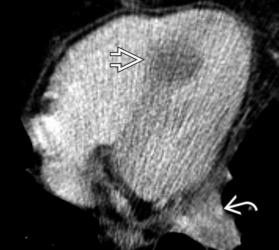

Metastases de mélanome VD et OD

Metastases de mélanome VD et OD